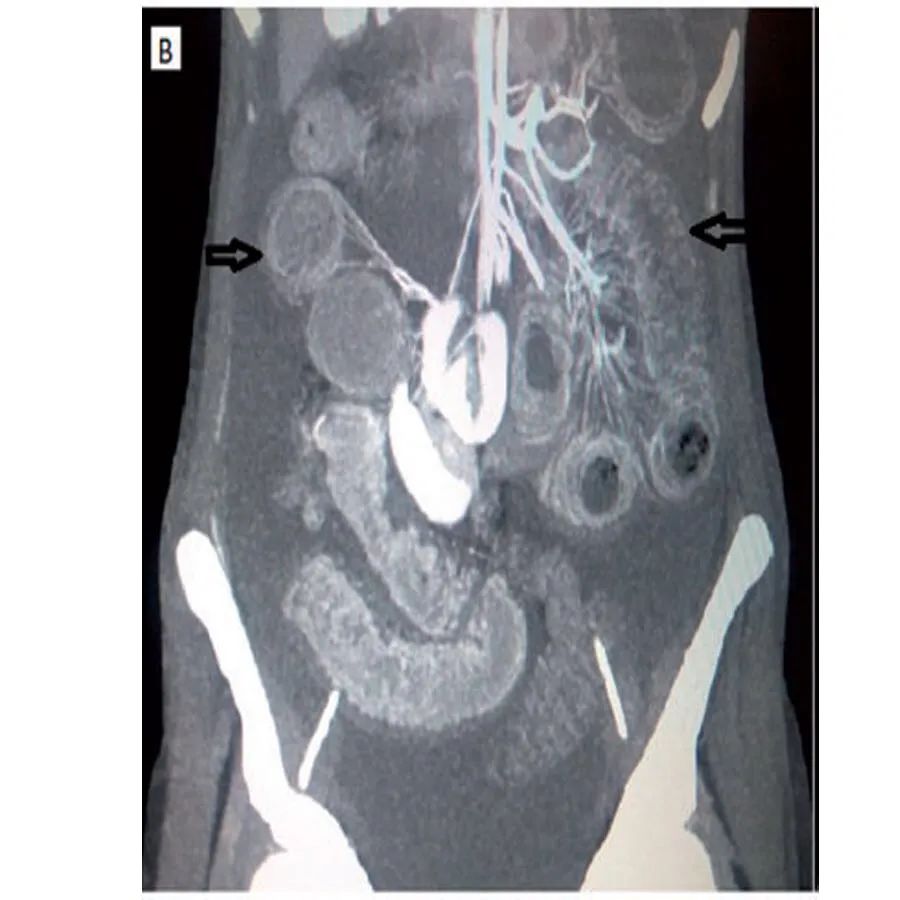

腹部CT显示腹水,肠管扩张,弥漫性肠壁分层,增强,双晕征(图1B),

腹部CT下正常人的肠管壁厚度不超过3mm,大于等于4mm则被认为肠管壁异常增厚。常见的CT表现包括肠壁局部或弥漫性增厚,肠壁异常强化,肠管呈梳状排列(梳状征),腹水及肠壁肿大。肠壁增厚通常是多灶性的,不局限于单个血管领域,因为肠系膜血管炎可能同时影响多条血管。增强CT(CTA)扫描清晰显示肠壁和腹部血管,提髙诊断的准确性。腹部增强CT肠管异常可表现为受累增厚肠段的黏膜层和浆膜层出现明显强化,而中间的肌肉层强化较低,犹如一个靶子,故称为“靶形征”或“双晕征”。肠系膜异常表现为肠系膜的血管增粗、增多,异常排列如“梳状”或“栅栏状这是系统性红斑狼疮合并肠系膜血管炎的常见征象。但需要注意的是,机械性肠梗阻,急性胰腺炎等也可引起肠管扩张,肠壁水肿增厚等变化,因此腹部B超,腹部站立位平片,腹部CT不仅可以帮助诊断,同时对于鉴别诊断也非常重要。与普通CT相比,肠道血管CT造影是诊断系统性红斑狼疮合并肠系膜血管炎的金标准,特别是当患者出现肠缺血、血栓等血管炎表现时,CT造影显示肠道节段性改变,正常肠道和异常肠段交替出现,呈多灶性的特征。